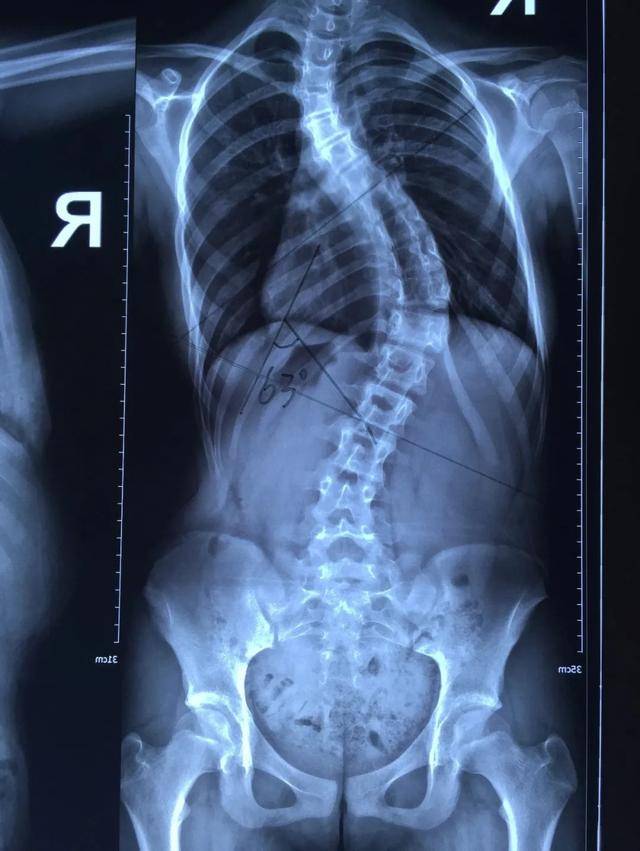

脊柱全长x光片显示胸腰段cobb角25°,身体有明显的倾斜趋势,剃刀背